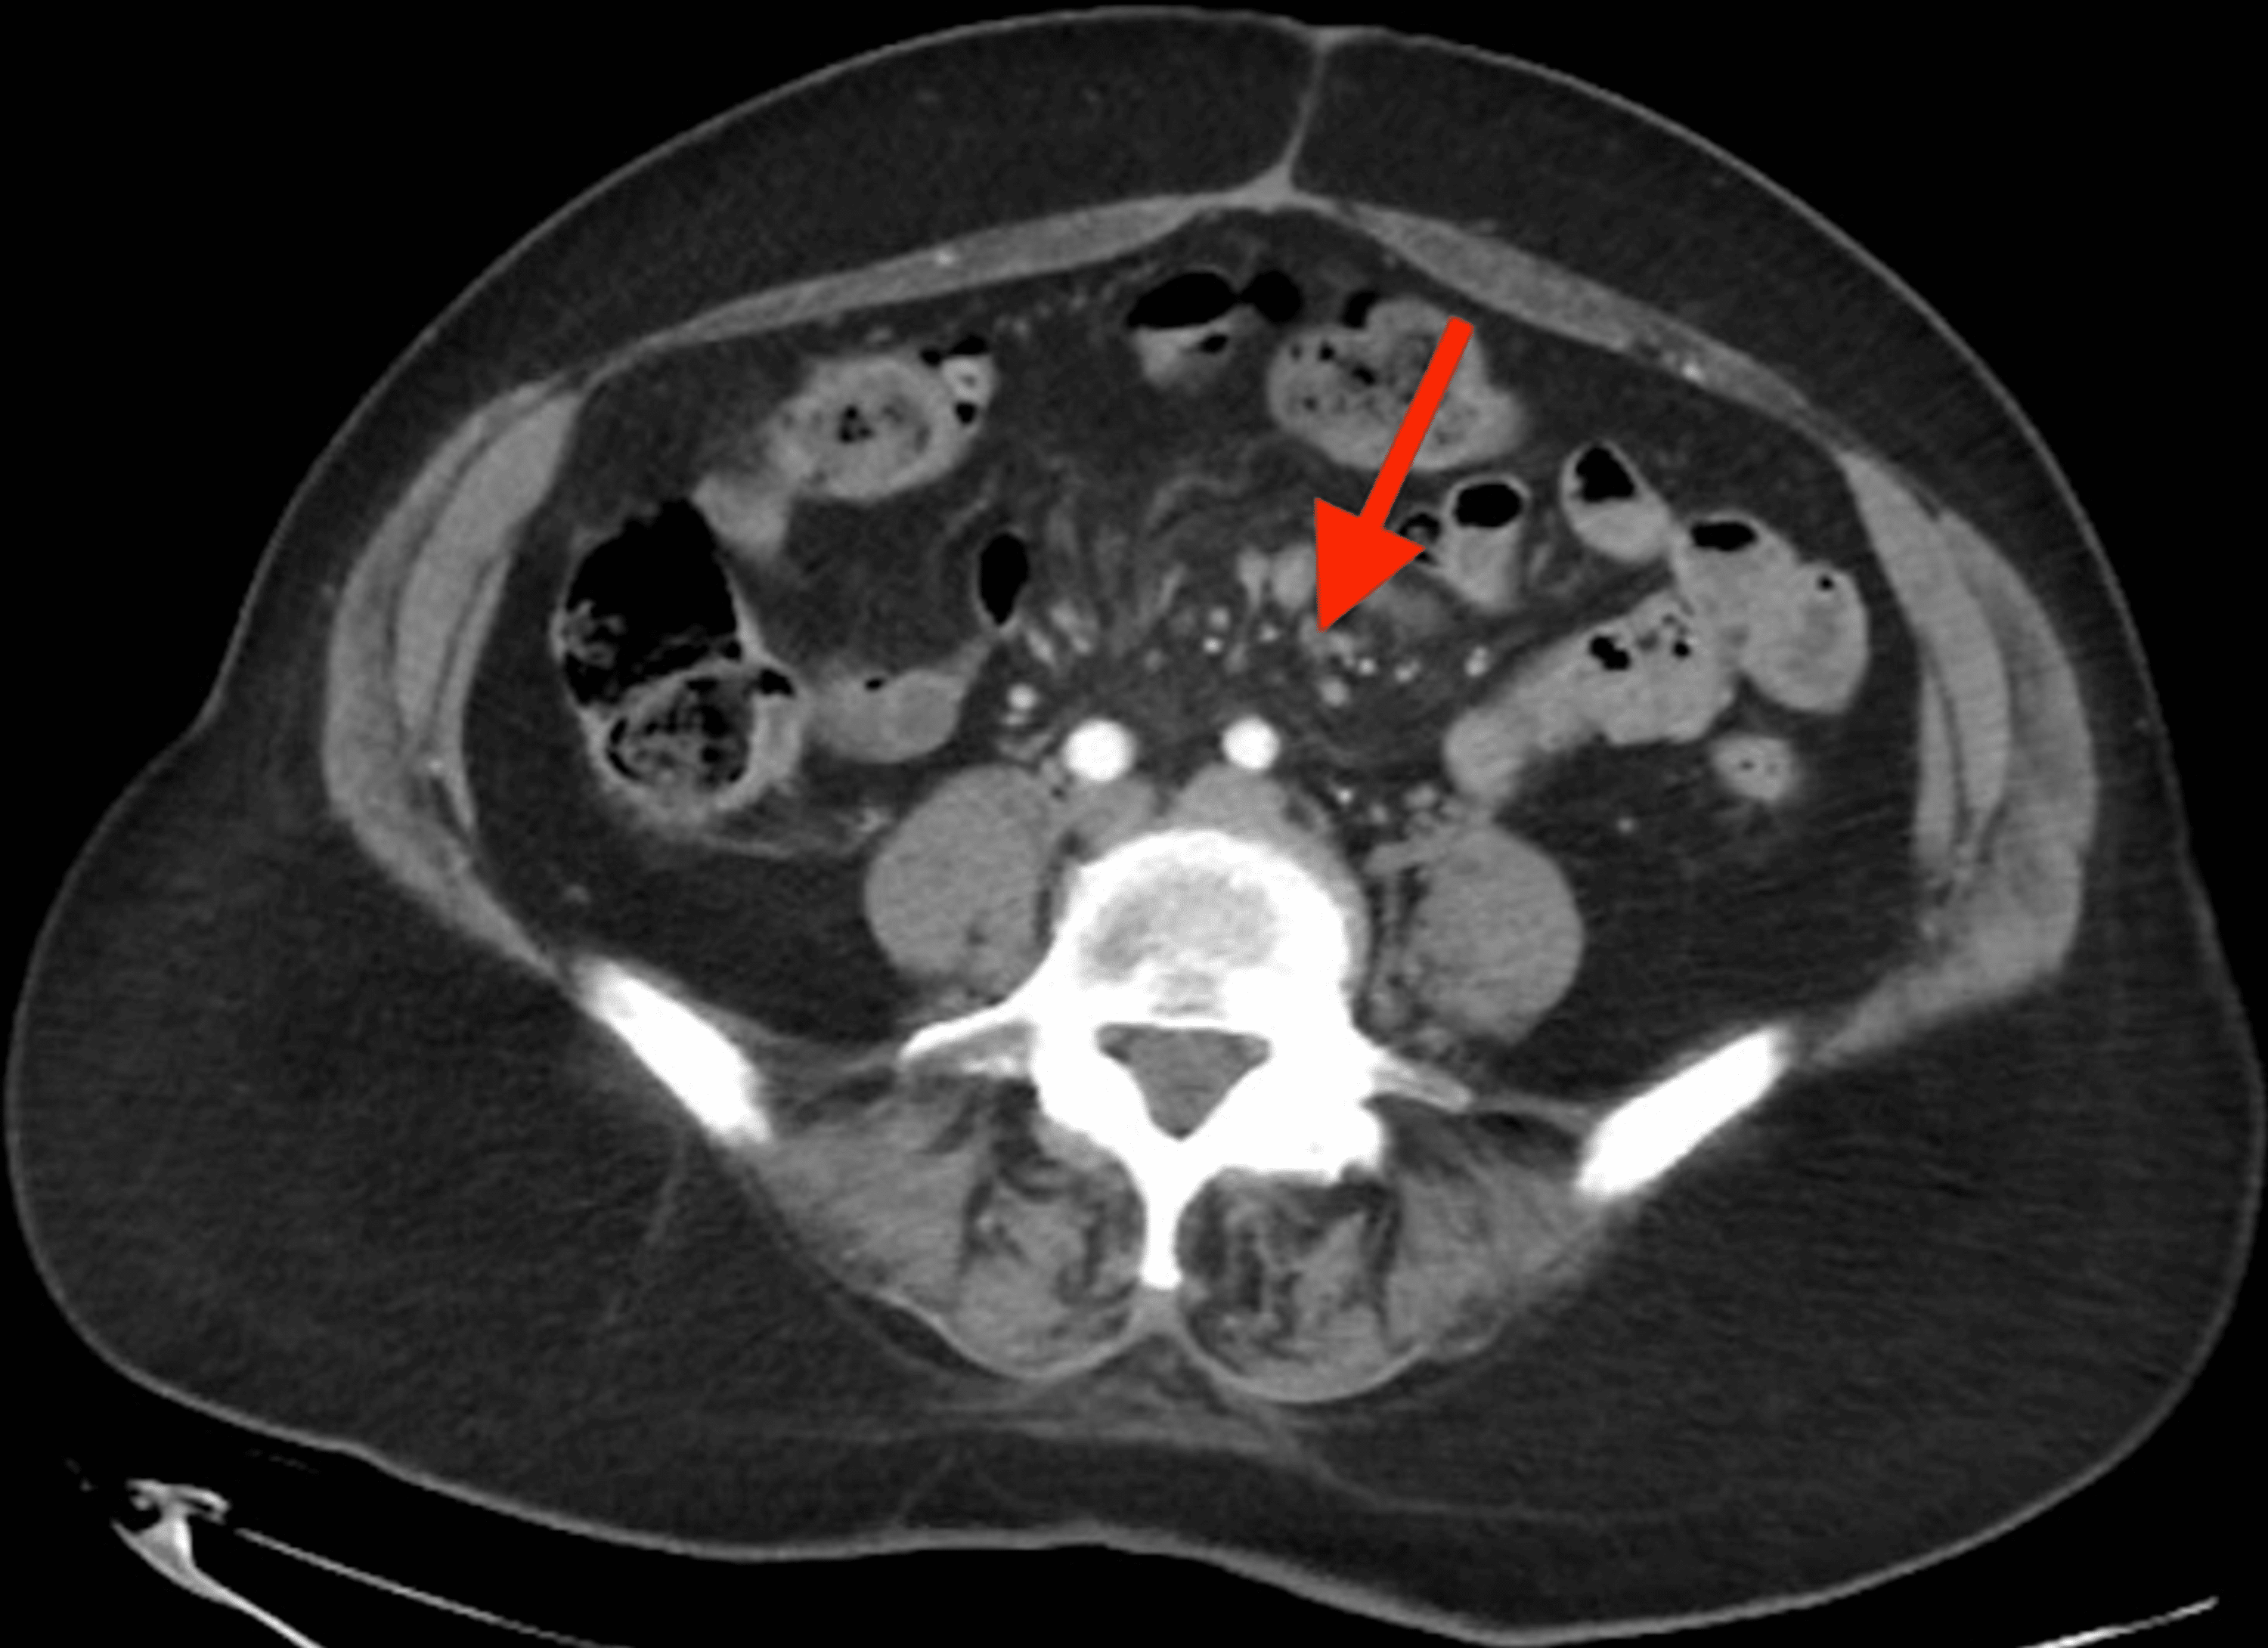

CT enterography Mesenteric hypervascular lesion in the mid ileum

CT enterography Mesenteric hypervascular lesion in the mid ileum Chalky White Lesions In Mesentery pathologic conditions of the mesentery can present a diagnostic challenge for radiologists because many. photograph of an axial image of the abdomen obtained on computerized axial tomographic (ct) assessment of a. sclerosing mesenteritis is a rare disease of the mesentery. the white chalky deposits are the saponificated remains of the fat in the mesentery and around. Chalky White Lesions In Mesentery.